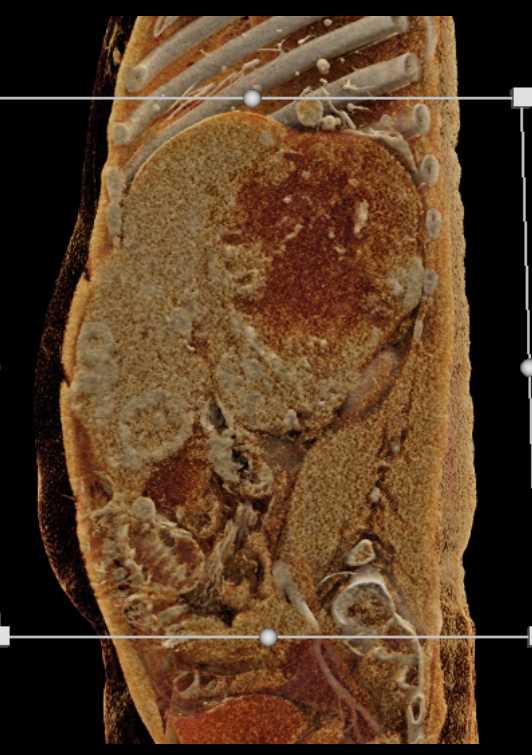

Extensive Neovascularity with Renal Cell Carcinoma and Metastases to Liver and Lung